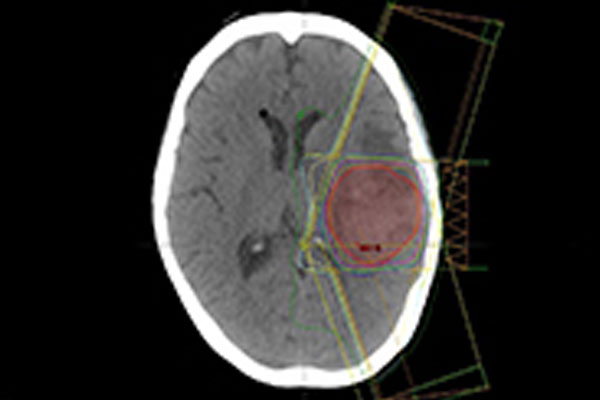

立體定位放射手術或治療 ❯